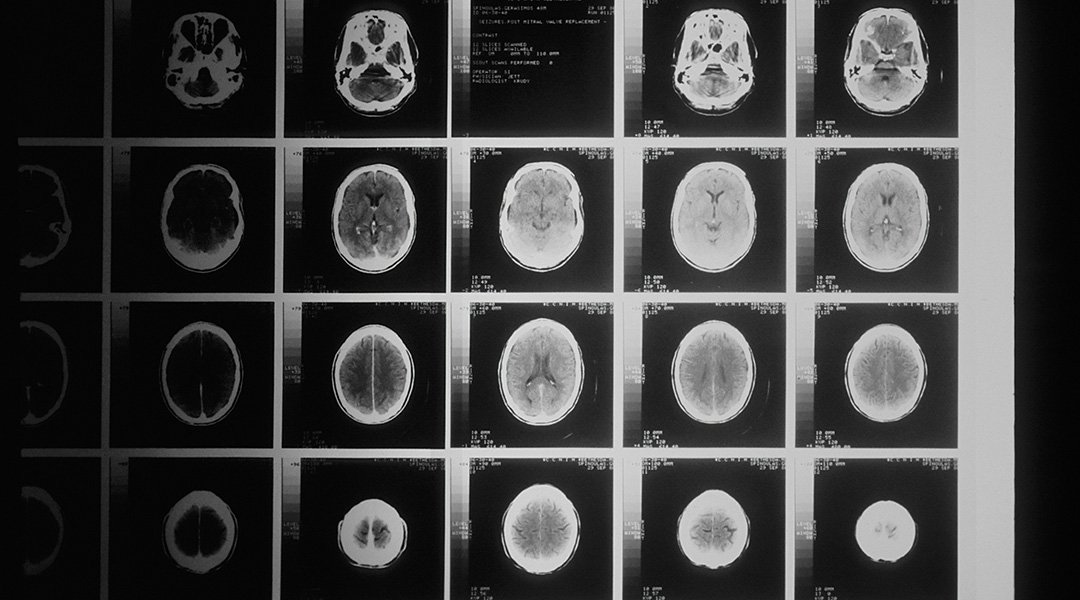

To train the model, Qiu and colleagues used a public cohort of 1,100 young people from diverse backgrounds and health conditions, aged between 8 and 21. Each participant’s data included questionnaire responses, interviews, and brain images obtained from a variety of neuroimaging techniques, including MRIs.

Neuroimaging is a useful diagnostic tool because certain changes in the brain are associated with psychiatric disorders. For example, loss of grey matter – the brain tissue involved in processing information, memory, emotions and movement – is often associated with early-onset psychosis.

The model extracted imaging signatures from brain images of adolescents in the training cohort that were related to four key aspects of mental illness: externalizing, psychoticism, fear, and anxiety. It then assigned numerical scores representing how well these signatures predicted general psychopathology and these four psychopathology aspects. The accuracy of the model was measured by how well the predicted scores matched the actual scores.

“Image markers can improve prediction accuracy by 25%. [using] “The model is designed after taking into account clinical characteristics,” Qiu said. After training the model, Qiu and team tested its performance on a larger cohort of 7,536 children between the ages of 9 and 11. When fed with only brain images, the model scored similarly to the training cohort, but when demographic and clinical characteristics were also taken into account, its predictive power dropped slightly.